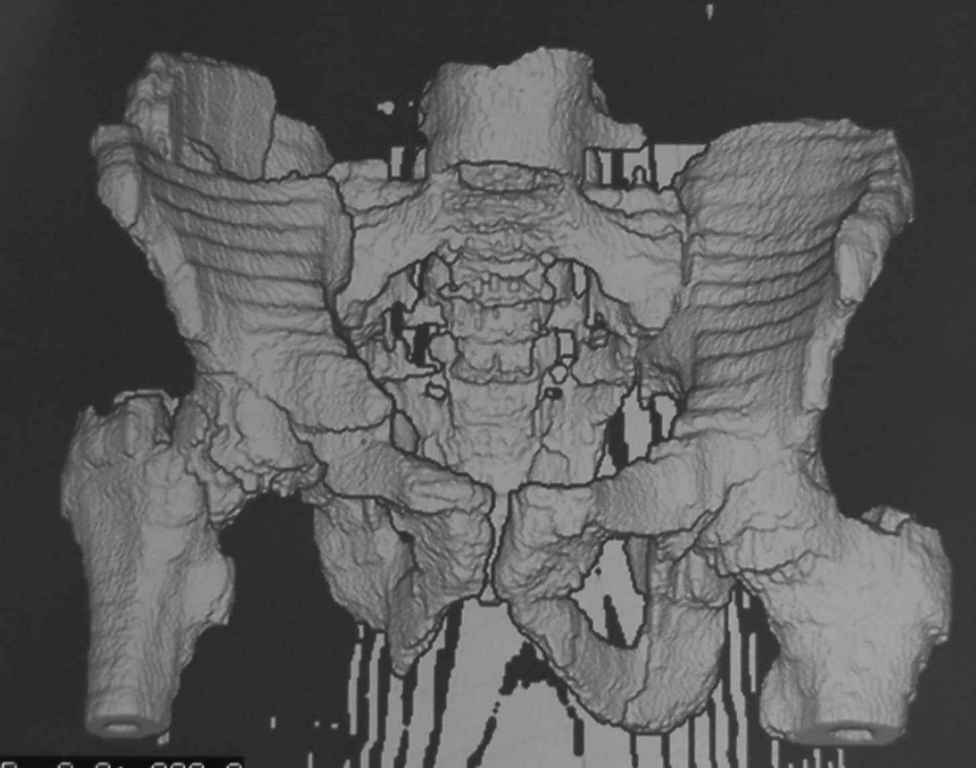

Ребенок 13 лет Перелом костей таза.

Уважаемые коллеги, в нашу клинику поступил ребенок 13 лет; травма четыре дня назад(падение с 5-го этажа). Помогите определиться с дальнейшей тактикой.